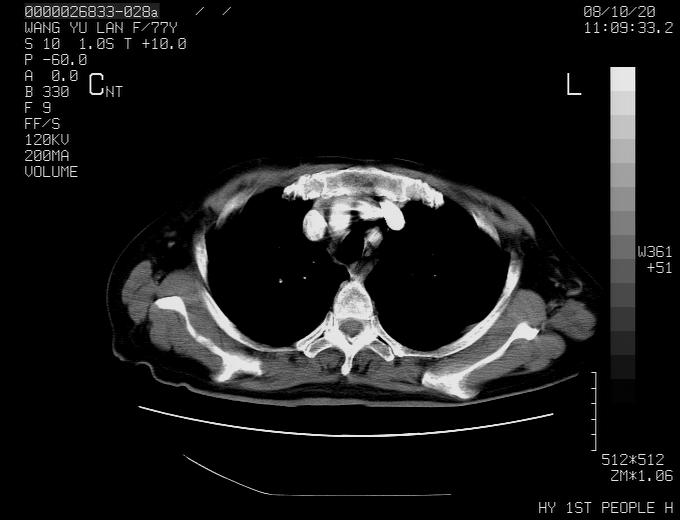

女性,77岁,胸部疼痛半月。左上肺团块影,本人考虑血管畸形,请分析

非常典型的avm(谢谢楼主,收藏了)

支持楼主,    但是做个矢冠状面成像就完美了

动脉期病灶近中线侧可见星芒状与大血管同等强化密度,支持考虑血管畸形伴血栓形成,动脉期不曲型,不除外周围型肺癌

1、考虑avm可能性大。2、纵隔有肿大淋巴结,左肺上叶有炎性病变,不排除肺癌并转移可能。